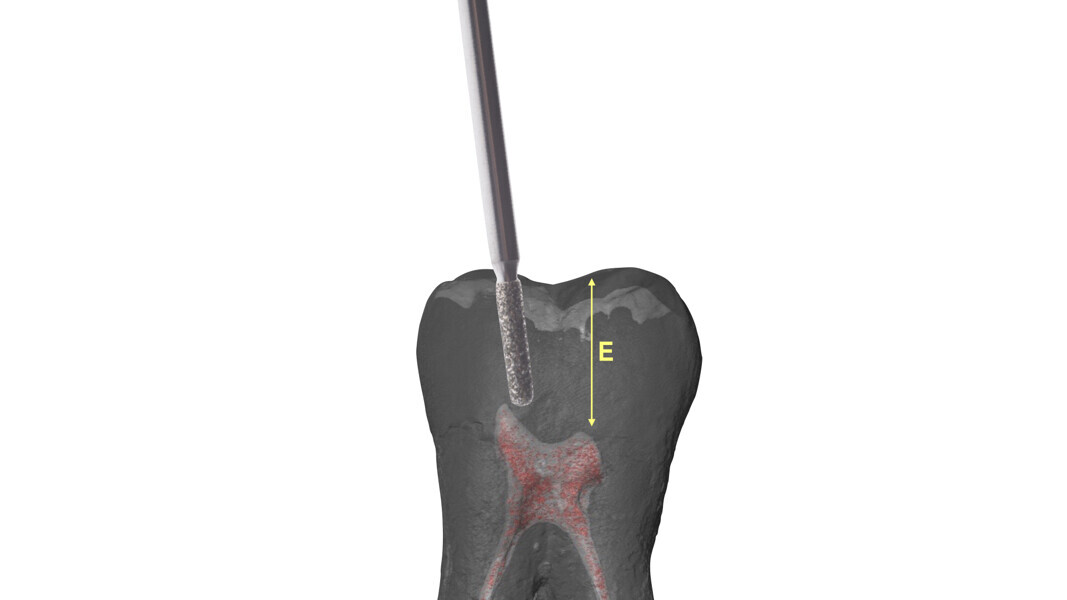

Fig. 13 : Emplacement des mesures effectuées par Deutsch et al.8, 9 sur une molaire inférieure analysée par micro-TDM (avec l’aimable autorisation du Prof. Elio Berutti).

Le principe du diamant fait référence à l’utilisation d’un certain type de fraise diamantée pour la phase de pénétration, en particulier dans les molaires supérieures et inférieures, ainsi que dans les prémolaires supérieures biradiculées. Deutsch8–9 associe des mesures morphologiques à la relation entre la surface occlusale, la hauteur, la position du plafond et du plancher de la cavité dans les dents pluriradiculées. Dans ces éléments, le plafond de la cavité pulpaire est situé au niveau de la JAC.

Dans les molaires, la distance entre la pointe d’une cuspide et le plafond de la cavité pulpaire est d’environ 6,3 mm, tandis que dans les prémolaires supérieures, elle est de 6,94 mm. La cavité pulpaire a une hauteur d’environ 1,5 à 2 mm et la distance moyenne entre le plancher de la cavité et la furcation est d’environ 3 mm (Tableau 1) (Fig. 13).